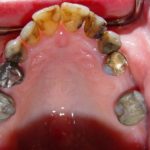

Case 6 – Upper Crowns / Lower Implants Makeover

- Before